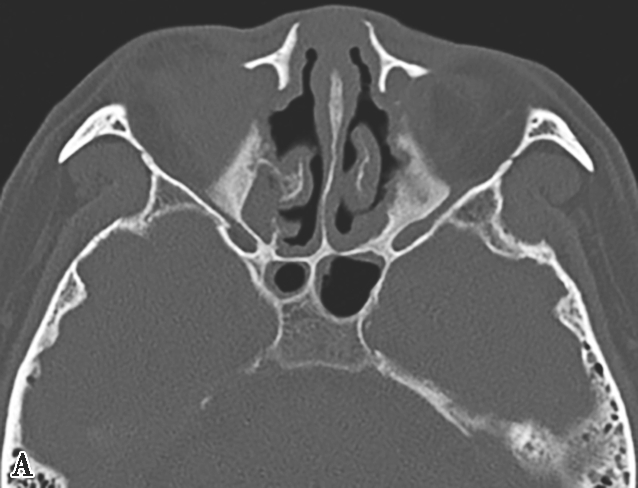

图1-3-21 真菌球

A~C.横断面CT骨窗、横断面软组织窗、冠状面CT骨窗,A、C示左侧上颌窦内充填软组织密度影,伴中央多发条状、云絮状高密度影,上颌窦窦口扩大,窦壁骨质增生硬化、肥厚;B示窦腔实变,中央高密度影显示更清楚;D~F.MRI横断面T 1 WI、T 2 WI及增强T 1 WI,示左侧上颌窦内软组织影,T 1 WI呈等、高信号,T 2 WI呈等、高信号,窦口区病变T 1 WI呈不规则形等、稍高信号,T 2 WI呈极低信号,增强扫描后窦口区病变无强化,周边黏膜呈线样强化